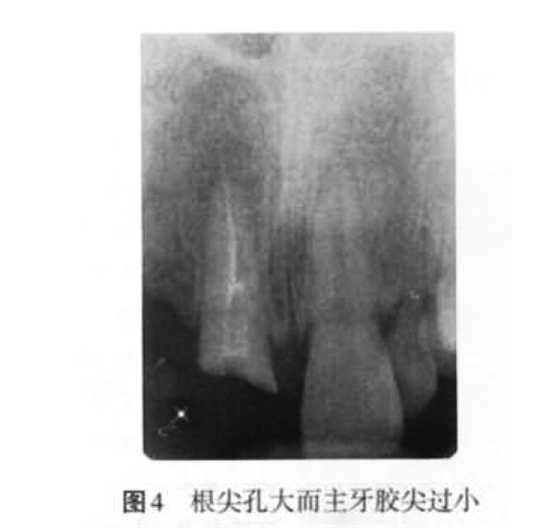

(2)超充原因:主要包括預(yù)備成形不良、根尖孔大而主牙膠尖過?。▓D4)、根管工作長度測量不準確、根充技術(shù)選擇不當(dāng)以及術(shù)者操作不當(dāng)?shù)仍颉?p style="text-align:center">